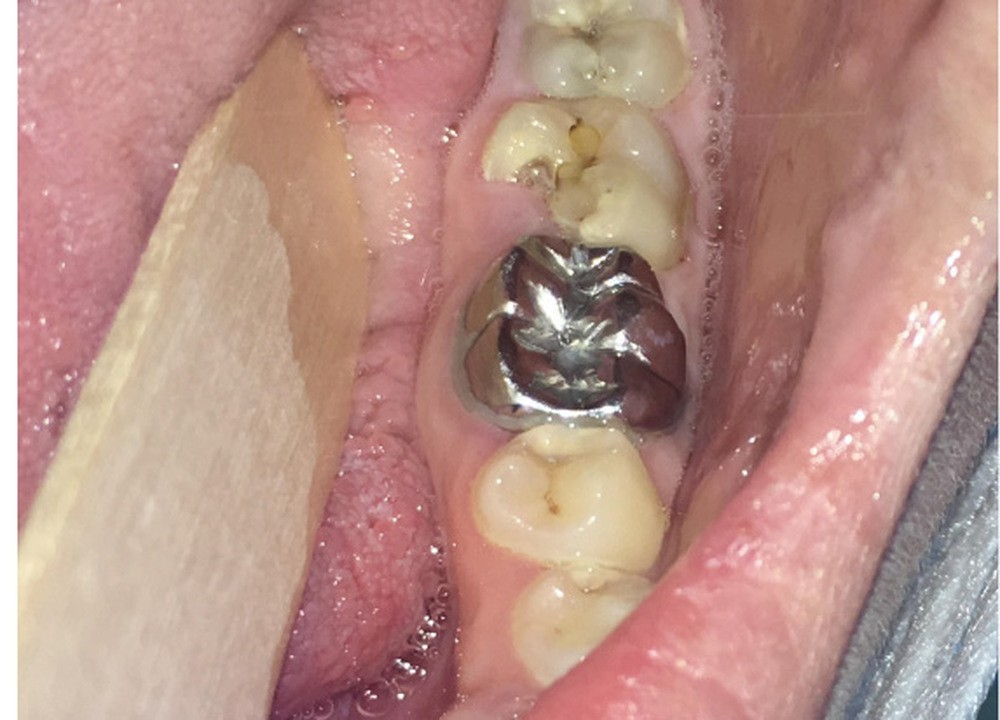

Pour les actes invasifs, une suspension de traitement pourra être discutée avec le médecin prescripteur, afin de réduire le risque infectieux au moment de l’acte, mais aussi en postopératoire [1, 2]. La thérapeutique sera reprise lorsque la cicatrisation sera complète. Il est évident que cette suspension de traitement ne doit pas altérer le pronostic de la pathologie et l’état général du patient. En cas d’urgence, les actes nécessaires doivent être entrepris sans délai (fig. 3).